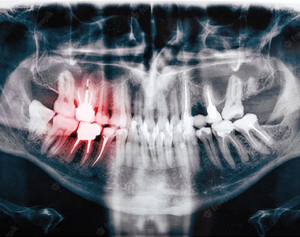

Understanding Your Wisdom Teeth As you grow, your mouth undergoes many changes. One significant change…

Understanding Dental X-Rays: Why They Matter and How We Keep You Safe Dental X-rays are…